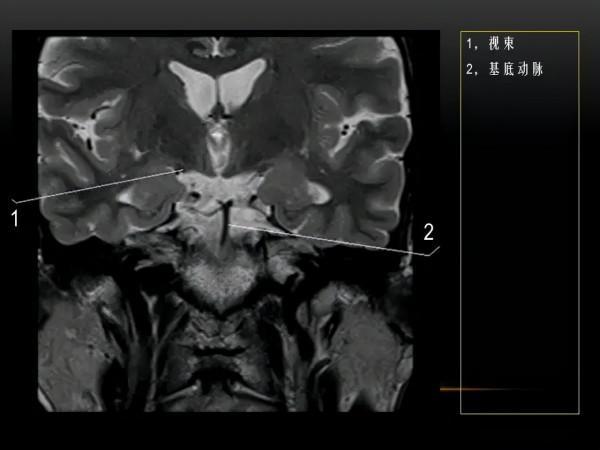

MRI下眼部及鼻竇的冠狀位解剖